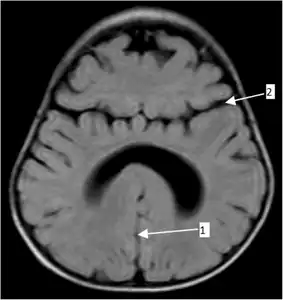

Semilobar holoprosencephaly-MRI shows incompletely interhemispheric fissure arrow 1 and partial fusion of frontal lobe arrow 2